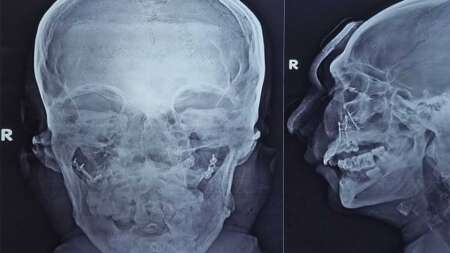

Management and care of a patient to combat disease or disorder.